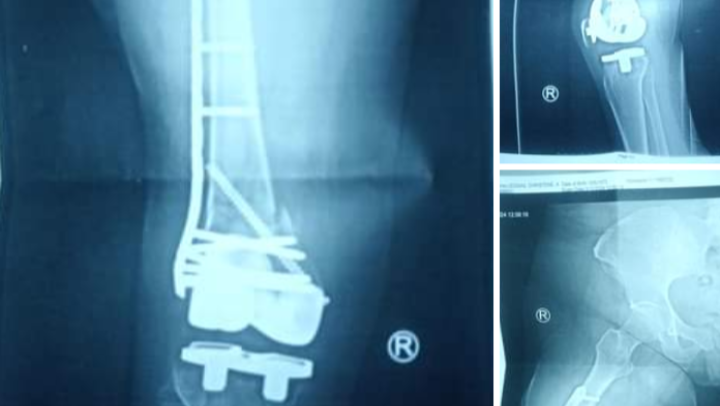

On January 10 2024 I was standing in front of Coens gas station on the South Side and a car pulled into the parking space in front of me and all of a sudden floored the gas and hit me and put me through the building. My story was on Channel 11 news, you can Google it for proof. I was taken to the hospital by ambulance I had a broken femur I needed 2 surgeries and was in the hospital and a nursing home for a month.

I was bed bound for 4 months unable to bare weight, at 6 months post op my bone is not healing.. today I got a bone stimulator that I have to wear for 24 hours a day for 6 weeks I can only take it off to shower when I go back to see my surgeon in 6 weeks if it's not showing signs of healing my doctor will decide weather he is going to do a bone graft or remove my femur from the break down and put in a metal rod, he said there is a very high risk of infection and a chance I could lose my leg. I am devastated.

- On January 11, 2024 I was pinned between a car and a brick building at Cohen's Gas Station on 24th and Carson Street on the South Side. I suffered a very complicated broken femur that I had to have a 5 hour surgery to repair, I now have an 8 inch rod in my leg and and so many pins and screws the surgery had to be stopped so they could get more parts brought into the operating room. I am in horrible pain, I cannot bare weight on my leg and may not be able to for up too 6 months. I'm now in a Skilled Nursing Facility and Rehabilitation Center I will need months of physical therapy. I was already on SSI and struggling due too a problematic knee replacement. This is going to set me back another year. I live alone. I have pets I must pay too be cared for they are my life and have never been without me. I will need home care when I am allowed to go home and what my insurance offers isn't enough it will have to be supplemented by me. The woman who hit me had no license or insurance and though she was arrested it will be a long time before I ever see any compensation if ever do.